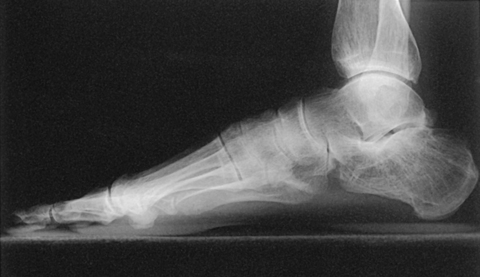

• Place the patient in the upright position, preferably on a low riser that has an IR groove. If such a riser is unavailable, use blocks to elevate the feet to the level of the x-ray tube (Figs. 6-53 and 6-54).

• If needed, use a mobile unit to allow the x-ray tube to reach the floor level.

• Place the IR in the IR groove of the stool or between blocks.

• Have the patient stand in a natural position, one foot on each side of the IR, with the weight of the body equally distributed on the feet.

• Adjust the IR so that it is centered to the base of the third metatarsal.

• After the exposure, replace the IR and position the new one to image the opposite foot.

Structures shown: The resulting image shows a lateromedial projection of the bones of the foot with weight-bearing. The projection is used to show the structural status of the longitudinal arch. The right and left sides are examined for comparison (Figs. 6-55 and 6-56).